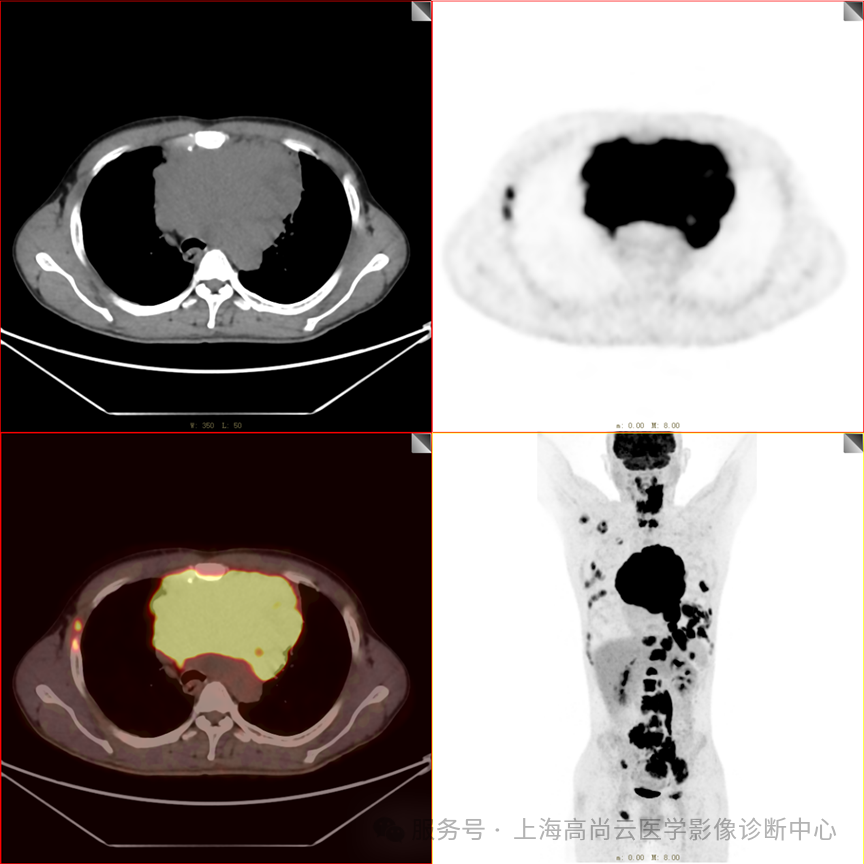

PET/CT 全身 MIP 图

PET/CT 融合图

PET/CT 检查显示:

前纵隔见巨大不规则软组织肿块,范围约 15.5 cm×10.2 cm×15.5 cm(上下径),边缘不规则,上下界约为胸骨柄上部至剑突水平,下方与心包分界不清,左前方侵入剑突水平前胸壁,其内密度不均匀,夹杂小片状低密度区,CT 值介于 17 Hu~44 Hu 之间,肿块整体呈 FDG 摄取弥漫性显著增高,SUVmax 约为 20.7。

纵隔(2R、4R 组)、内乳区(左侧)、左侧心膈角区及膈脚后间隙见多发增大淋巴结影,FDG 摄取显著增高,最大约 3.3 cm×2.0 cm,SUVmax 约为 23.0。心包左侧、大血管间隙及左侧胸膜见多发结节状及条块状 FDG 摄取增高影,SUVmax 约为 20.5,CT 见不规则软组织增厚影,边界清楚。

颈 2~6 椎体、胸(6、7、8、11、12)椎体、腰 1~5 椎体、右侧肱骨、右侧肩胛骨、双侧肋骨多处、骨盆诸骨、右侧股骨见多发不规则结节状及团块状 FDG 摄取增高影,SUVmax 约为 17.9,CT 于上述部位见部分骨质密度轻度增高,大部分骨周围伴有软组织肿块形成,部分侵犯左侧腰大肌及双侧竖脊肌下部,部分累及相应椎管。